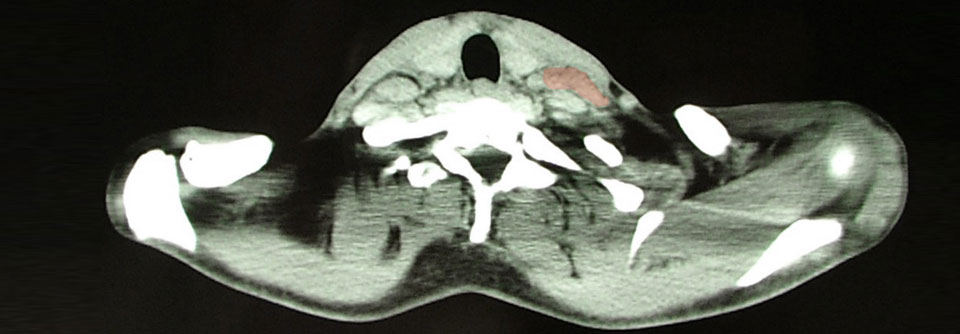

Wirksam, meist verträglich und ermutigend: So beschrieben zwei Referenten neue Therapien, die für Patienten mit Hodgkin-Lymphom relevant werden könnten. Sowohl auf CD30-CAR-T-Zellen als auch auf das Antikörper-Wirkstoff-Konjugat Camidanlumab-Tesirin sprachen viele stark Vorbehandelte an.

Bei einigen Krebsarten kommen CAR-T-Zellen und Antikörper-Wirkstoff-Konjugate bereits zum Einsatz, auch für das Hodgkin-Lymphom wird beides erprobt. Zu den Vorteilen von CAR-T-Zellen gegenüber den „Molekülen“ zähle unter anderem, dass sie das sequenzielle Abtöten mehrerer Targets vermitteln, erinnerte Prof. Dr. ­Natalie ­Grover von der University of North Carolina in Chapel Hill. Außerdem könne man sie so verändern, dass sie einen „immune escape“ der Tumorzellen überwinden. Gerade gegen CD30 gerichtete CAR-T-Zellen bieten sich an: Das Antigen wird von Hodgkin-Lymphomen universell exprimiert, in normalem Gewebe dagegen nur sehr wenig, so die Referentin.